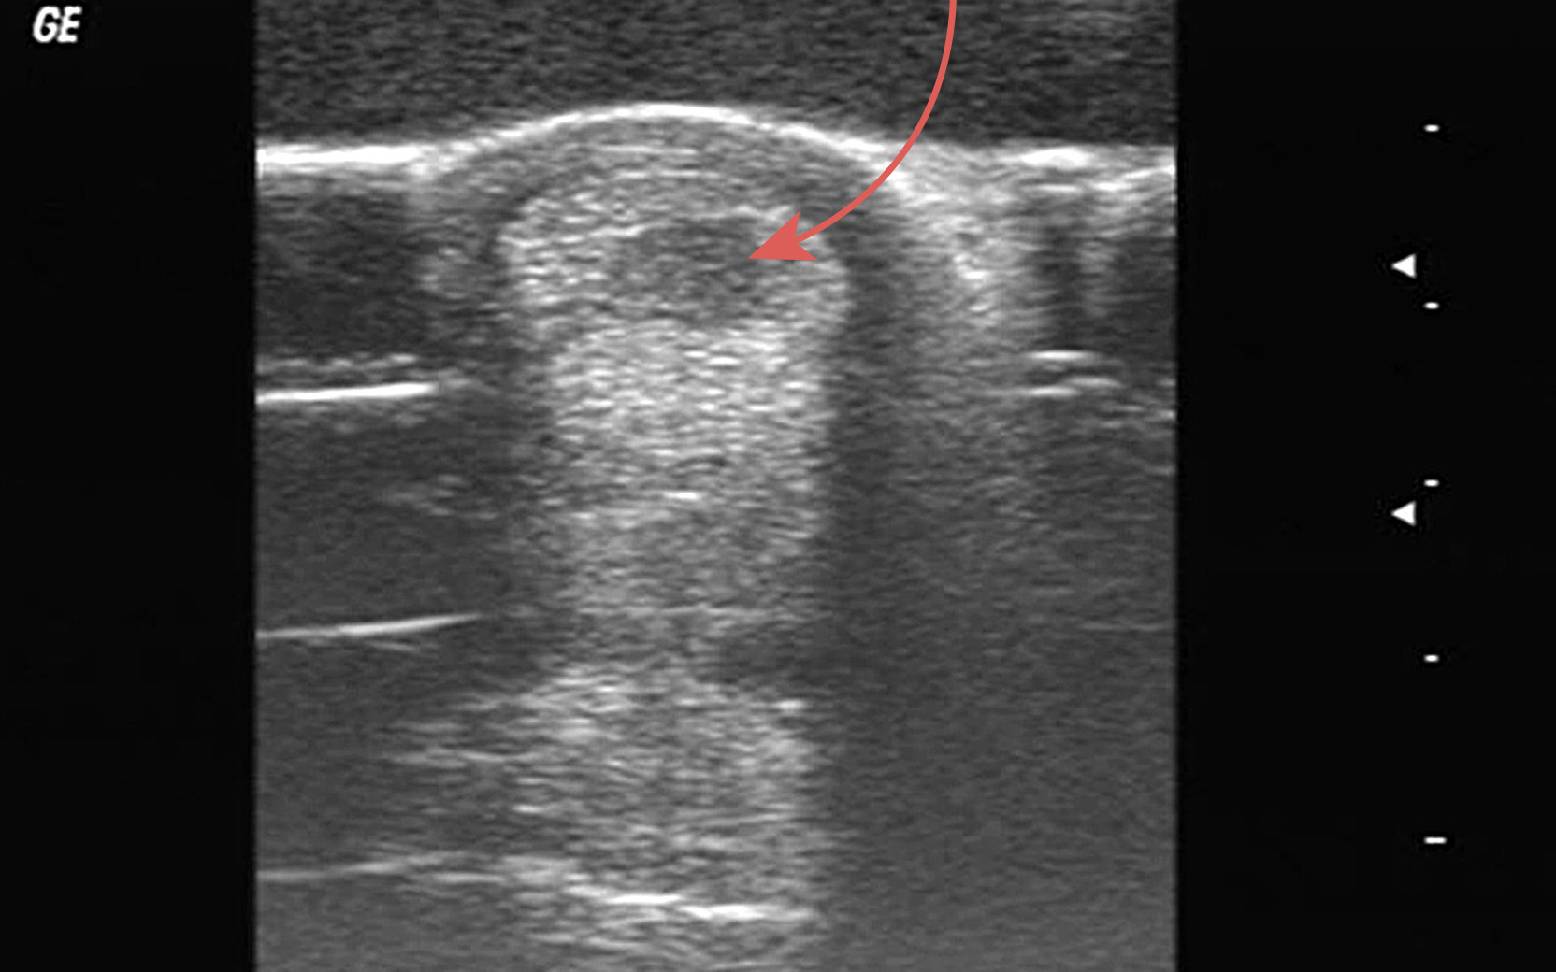

Bei Vorliegen obiger Symptome muss immer umgehend eine tierärztliche Untersuchung erfolgen, um zu verhindern, dass das Gewebe durch weitere Belastung zusätzlich geschädigt wird. Durch die Lahmheitsuntersuchung und Feststellung der Symptome alleine kann der Tierarzt jedoch noch keine sichere Diagnose stellen. Nur mit Hilfe einer Ultraschalluntersuchung ist ein Sehnendefekt zu diagnostizieren und exakt zu lokalisieren.

Mit Hilfe regelmäßiger Ultraschalluntersuchungen kann der Heilungsprozess begleitet und überwacht werden und je nach Ultraschallbefund wird tierärztlich entschieden, wann wieder mit kontrollierter Bewegung begonnen werden kann. Die Einhaltung eines genau auf das betreffende Pferd und den Umfang des jeweiligen Schadens abgestimmten Bewegungsplans ist mindestens genauso wichtig wie die eigentliche Therapie, denn nur so erlangt die regenerierte Sehne ein Höchstmaß an Belastbarkeit zurück.